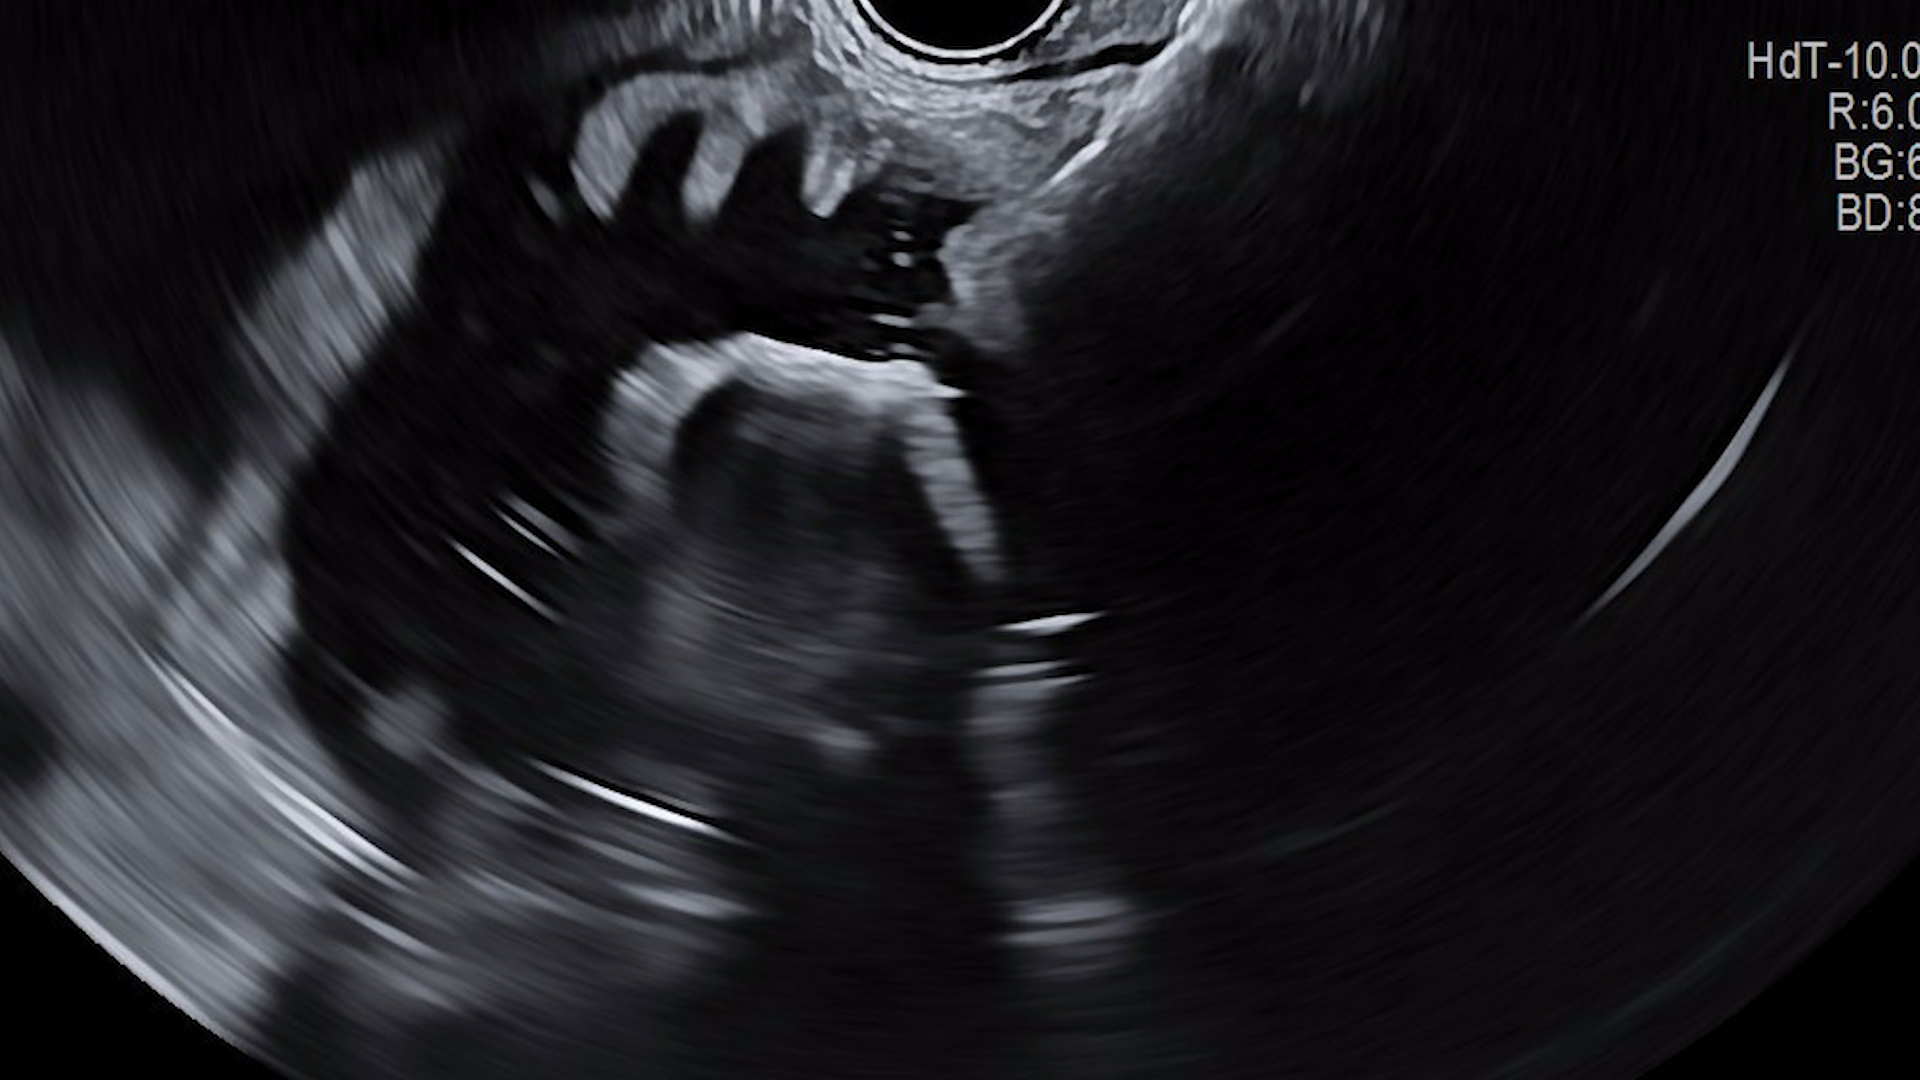

Ținând cont de vârsta pacientului, comorbidități și de refuzul intervenției chirurgicale, s-a decis efectuarea unei gastrojejunoanastomoze ghidate ecoendoscopic, cu stent expandabil metalic de apoziție (de tip LAMS), procedura fiind efectuată în condiții de protezare respiratorie (anestezie generală cu intubație oro-traheală). S-a utilizat tehnica cu sondă nazoenterală, cu instilarea la nivel enteral a aproximativ 400ml de ser fiziologic cu albastru de metilen pentru distensie intestinală (Fig. 2). După retragerea sondei, s-a introdus ecoendoscopul linear la nivel gastric și a fost identificată ansa de intestin subțire dilatată. Puncția a fost efectuată după verificarea în prealabil a traiectului, prin examinare Doppler pentru evitarea vaselor, fiind introdus un stent LAMS (HotAxios, Boston Scientific) de 20/10mm, sub ghidaj ecoendoscopic și radiologic (Fig. 3). După eliberarea flanșei proximale, a fost evidențiat serul fiziologic cu albastru de metilen la nivel gastric. S-a efectuat tranzit baritat pentru permeabilitate (Fig. 4), cu aspect favorabil. Un examen CT efectuat la 24h, cu administrare de substanță de contrast oral, a evidențiat permeabilitatea gastrojejunoanastomozei, fără extravazare de substanță de contrast (Fig. 5).